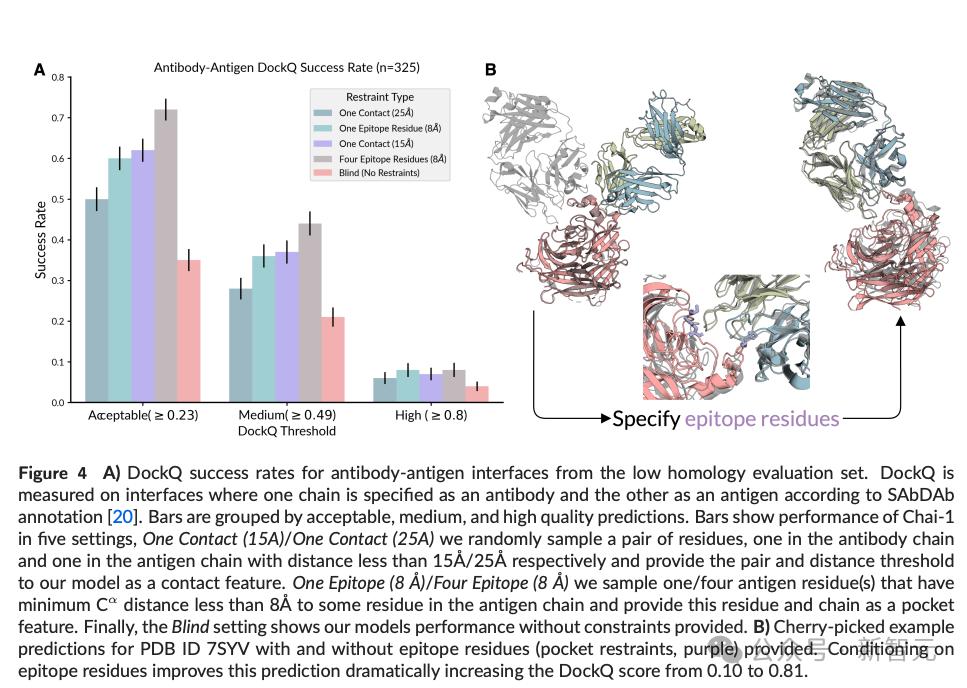

对比实验中发现,提供约束条件后,甚至可以为模型性能带来两位数的提升(图4A);但为了防止模型过于依赖约束条件导致过拟合,训练时对这些特征采用了dropout。

比如表位的约束——即使只有少量的接触点或结合袋残基的信息,也能使抗体-抗原结构预测的准确率翻倍,让AI在抗体工程中的角色变得更加实用。